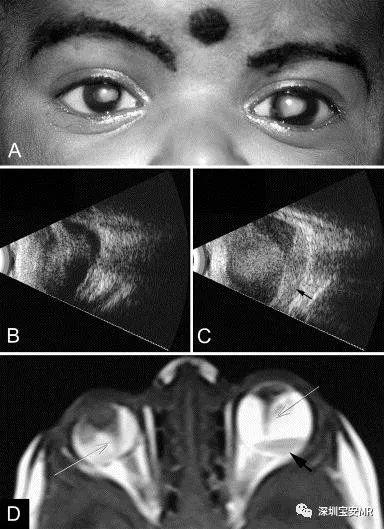

case1

case1。A,右眼小眼球(角膜直径9.5 mm),双眼晶状体后肿块。由于长期眼压升高,左眼显示角膜增大(角膜直径11.5 mm)。B、C、B超显示右眼(左眼)为帐篷状全视网膜脱离,左眼(右眼)为全视网膜脱离并伴有视网膜下积液(箭头)。D、MRI右眼可见小眼炎,左眼玻璃体信号普遍增高,并伴有液平面(黑色箭头),双眼显示Cloquet管(白色箭头)。 医学百科网 | YxBaike.Com